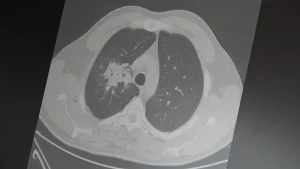

100’den fazla bilimsel çalışmanın incelendiği kapsamlı analizlere dikkat çeken Özkaya, elektronik sigaraların özellikle temas ettiği akciğer ve ağız bölgelerinde kanser riskini artırabileceğine dair güçlü bulgular bulunduğunu belirtti.

2024 yılında yayımlanan bir çalışmaya da değinen Özkaya, hem geleneksel sigara hem de elektronik sigara kullanan bireylerde akciğer kanseri riskinin, sadece sigara içenlere göre dört kat daha fazla olduğunun bildirildiğini kaydetti.